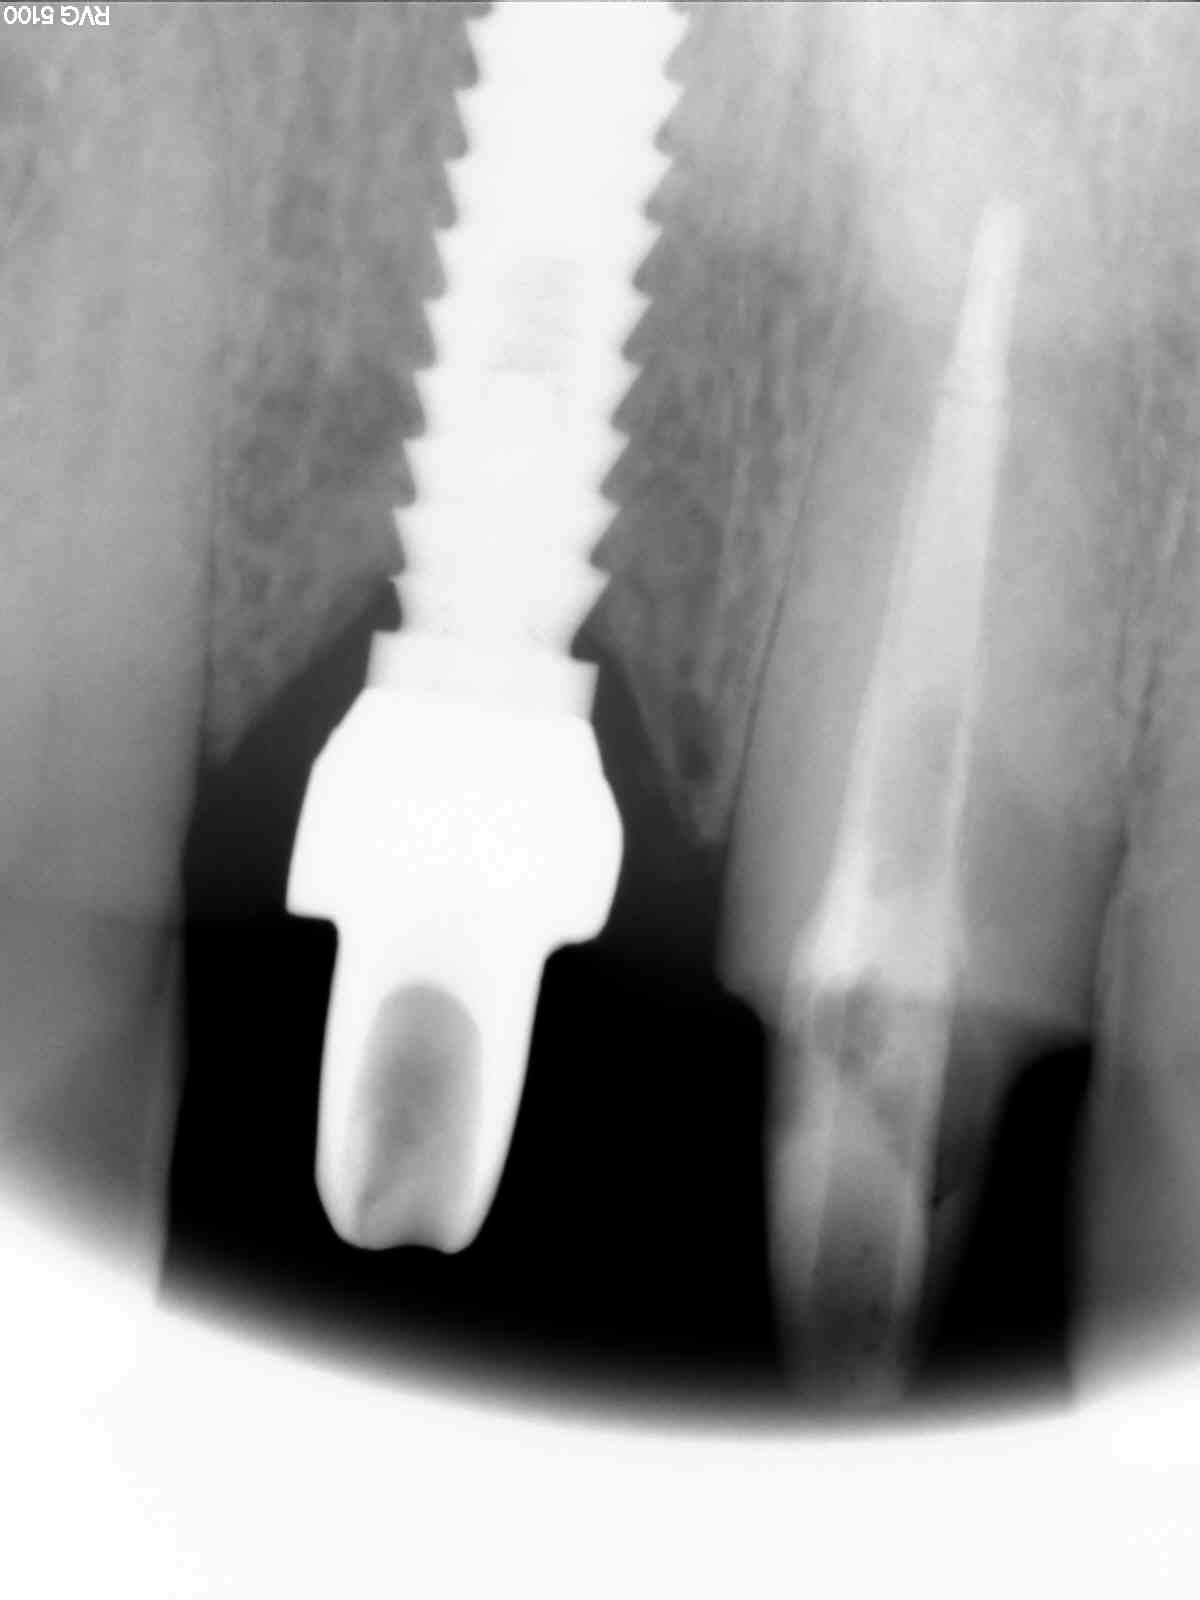

Este paciente llegó al consultorio con reabsorción dentinaria (pérdida de la estructura del diente). Por ello se le extrajo el diente, se le colocó un implante y se restauraron las piezas con coronas de cerámica pura.